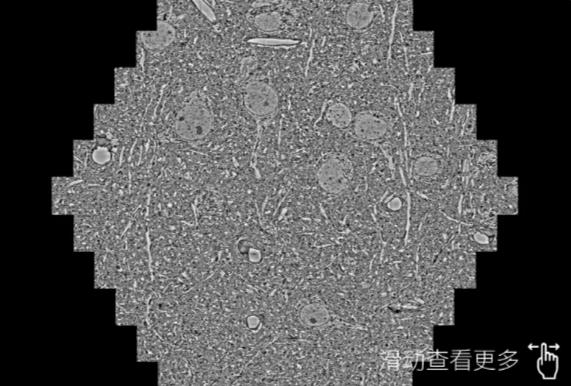

鼠脑切片。左图使用朔州蔡司朔州扫描电镜MultiSEM706对165μmx143pm面积区域成像,耗时仅需1.5秒。右图为鼠脑切片中30μm区域放大效果。样品由芝加哥大学B.Kasthuri提供。

使用蔡司高速朔州扫描电镜MultiSEM对1mm²人脑皮层组织进行高分辨成像,并对其中的各种细胞结构进行三维重构分析。左图展示了2x3mm²组织平面中锥体神经元的三维重构效果。右图显示了局部体积神经元三维重构。图像由哈佛大学chtman实验室提供,渲染图由D. Berger 制作。